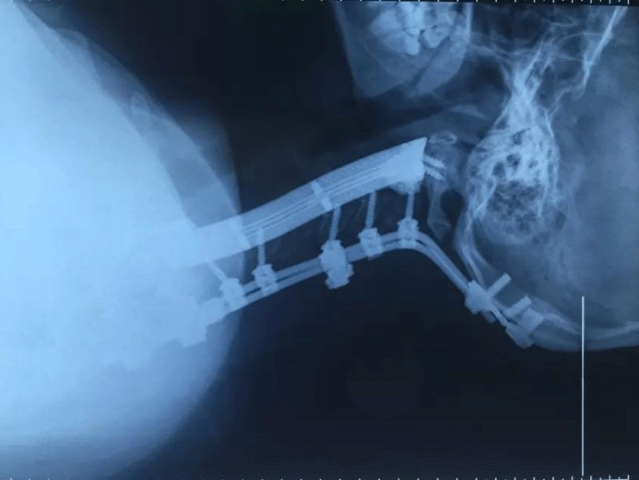

(Photo/Thepaper.cn)

Surgeons at a hospital in Shanghai, China, have completed what is claimed to be the world’s first cervical vertebrae replacement operation with additively manufactured titanium bones, reports the People’s Daily Online.

The 28-year-old patient was diagnosed with chondrosarcoma, a rare type of bone cancer that attacks cartilage, in May 2017. A tumour was found on her neck, encroaching on six of the seven bones of the cervical vertebra. As the cancer is prone to relapse and chemotherapy is less effective, doctors at Shanghai Changzheng Hospital decided to remove all six bones and replace them with additively manufactured alternatives.

The team, led by specialist spinal surgeon Xiao Jianru, are said to have spent three weeks building the artificial bones. They chose titanium alloy and used Additive Manufacturing technology to customise them for the patient.

Shanghai Changzheng Hospital is the largest centre for spinal tumour treatment in China. Over 1,000 operations are conducted every year at the hospital. Following two operations, lasting a total of 13 hours, the patient is said to be recovering slowly. She is now able to walk, but still has difficulty turning her head normally.